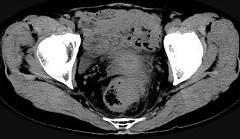

问题 男,56岁,排便形状改变,便不尽感,CT检查如图所示,下列说法正确的是 ( )

选项 A.肠壁上有蒂状新生物 B.其表面光滑,边界清楚 C.肠腔未见狭窄 D.此为直肠息肉 E.此为直肠癌

答案 E